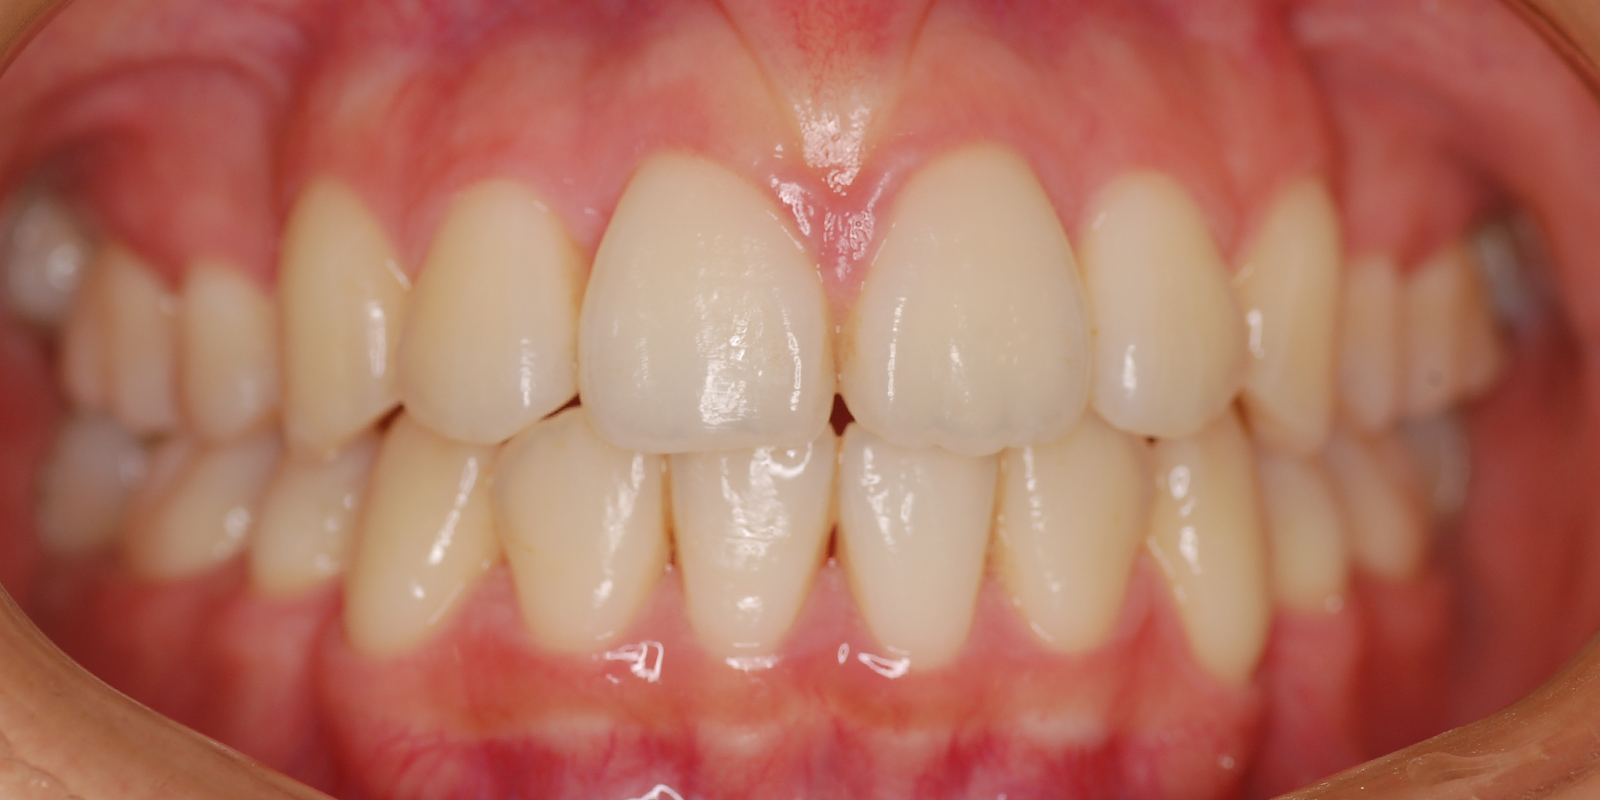

術前

術後

| 主訴 | 噛み合わせが深い |

| 診断 | アングルⅡ級2類Deep bite |

| 初診時年齢 | 8歳3か月 |

| 装置 | EF |

| 抜歯・非抜歯 | 非抜歯 |

| 治療期間 | 2年 |

| 通院回数 | 約12回 |

| 治療費 | 25万円 矯正歯科治療は公的医療保険の適用外の自費(自由)診療となります |

| 治療のリスク | ・装置を使用しなければ効果が出ない ・上下前歯に痛みが出ることがある ・取り外しのためなくすことがある |